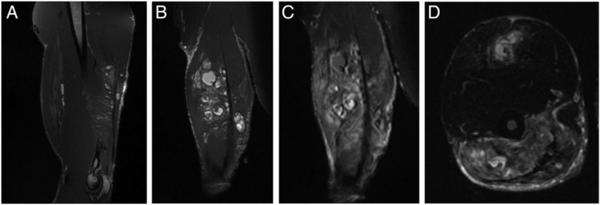

La resonancia magnética que se le realizó arrojó como resultado la presencia de quistes en sus músculos. Finalmente, el hombre confesó: había inyectado aceite de coco en su bícep derecho. Creía que de esa forma los glóbulos grasos aumentarían mientras esperaba que su tendón sane. Sin embargo, el aceite produjo una coagulación lo que provocó una lesión proteica.